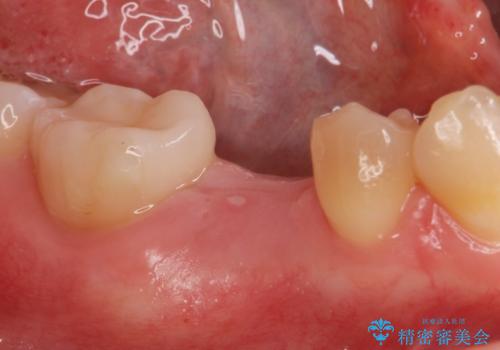

併用して銀歯も気になるとの事でしたのでセラミック治療も行いました。

適合の良いセラミックが入りました。

- インプラント体、アバット、仮歯、ジルコニアクラウン・42.9万円 e-maxインレー・7.7万円 費用は治療当時の料金となります